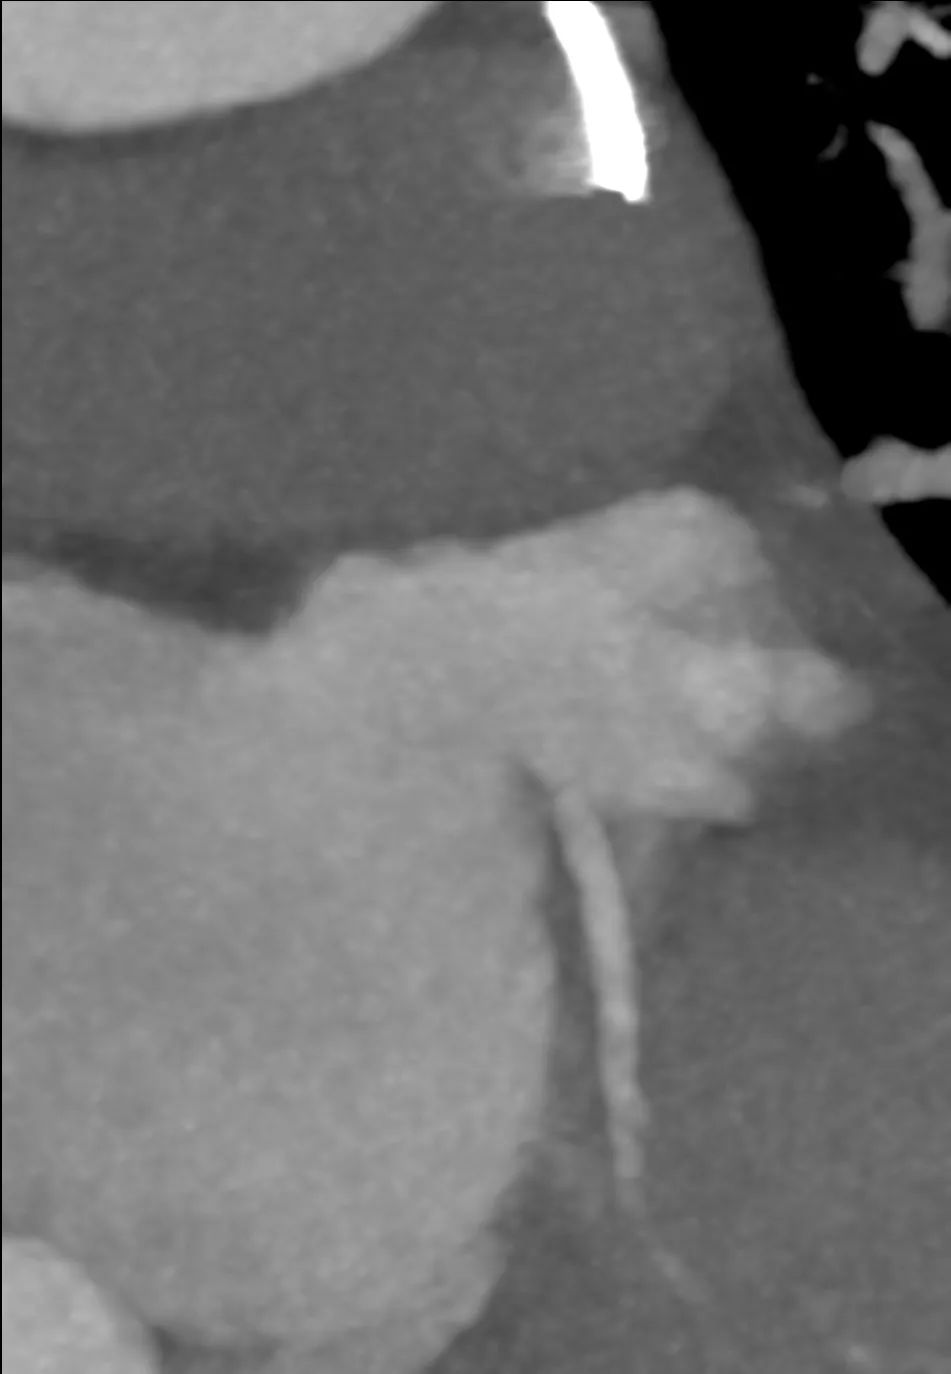

左冠风险评估

瓣膜内22mm球囊后扩张,左冠无显影

LM烟囱支架植入4.0*30mm